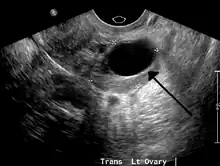

Transvaginal ultrasonography of a hemorrhagic ovarian cyst, probably originating from a corpus luteum cyst. The coagulating blood gives the content a cobweb-like appearance.